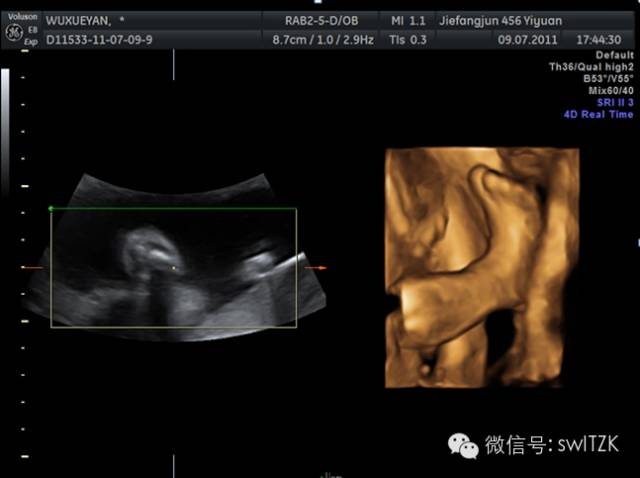

三个月时候的妊娠,可以清晰的看见脐带以及刚刚成形的胚胎结构。

四月妊娠,可以看到一个大致成形的胎儿,刚刚分化出来的四肢。